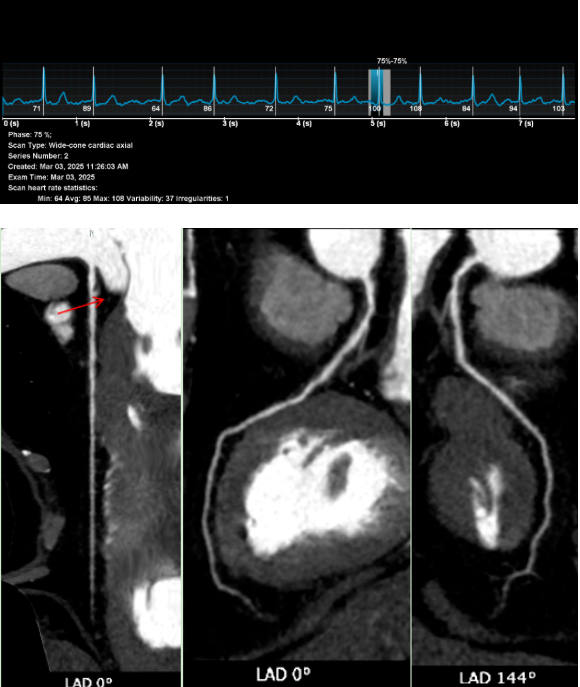

经过一系列检查,辽宁一脉阳光医学影像诊断中心医生通过冠状动脉CT血管成像(CCTA)发现,他的左冠状动脉前降支近端出现了中度狭窄,同时还伴有心肌桥的形成。这个结果,正是典型冠心病的表现。

在张大爷的病例中,CT影像清晰显示了他的左冠状动脉前降支近端有中度狭窄。前降支是冠状动脉中最重要的一支,负责左心室大部分血液供应。这里的狭窄,直接导致了他胸痛胸闷的症状。更特别的是,检查还发现了“心肌桥”,当心脏收缩时,心肌会压迫血管,进一步加重血流受限。这种结合了狭窄和心肌桥的情况,在老年患者中并不罕见,但也增加了诊断和治疗的复杂性。

从影像学角度看,CT冠状动脉成像是无创诊断的金标准之一。它通过三维重建技术,将冠状动脉的形态、狭窄位置和程度直观呈现出来。

对于张大爷这样的高龄患者,传统CT扫描面临两大挑战:一是患者无法长时间屏气,二是心律不齐会影响图像质量。然而,宽体探测器CT技术的应用,完美解决了这些问题。这种设备扫描速度极快,仅需0.3秒就能完成心脏成像,患者无需屏气,可自由呼吸,且心率波动对图像质量影响极小。

在张大爷的检查中,医生利用宽体探测器CT获得了高质量的冠状动脉图像。图像清晰显示了狭窄的位置和程度,以及心肌桥的形态。这种技术的优势在于其高时间分辨率和空间分辨率,能够“冻结”心脏运动,避免运动伪影,从而提供诊断所需的精细解剖信息。此外,低剂量扫描技术的应用,还减少了辐射暴露,特别适合老年和体弱患者。